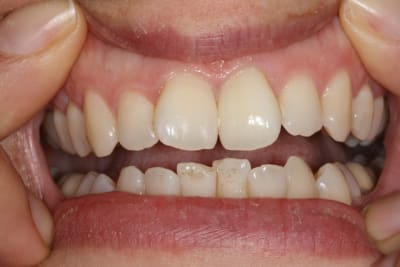

Cas simple et pourtant ... j'ai été obligé de prendre un risque . Lequel ?

PS/ Je prolonge le ttt jusqu'à la semaine prochaine en espérant gagner encore un poil sur l'opacité .

C'est un blanchiment unitaire sur dent vivante ayant eu traumatisme.

C'est un blanchiment interne comme si l'endo était faite (après recherche effrénée d'un hypothétique canal), et après contrôle +++ d'une isolation +++ . La patiente n'a aucun souvenir d'un traumatisme sur cette dent .

Si on décide d'être le moins invasif , j'ai jugé raisonnable de tenter quand même malgré l'impossibilité de repérage de l'entrée du canal . Faire une facette c'est passer un cap , et je n'ai de prothésiste capable de reproduire les stries visibles sur la photo de départ de tout façon donc je n'ai compté que sur moi même .